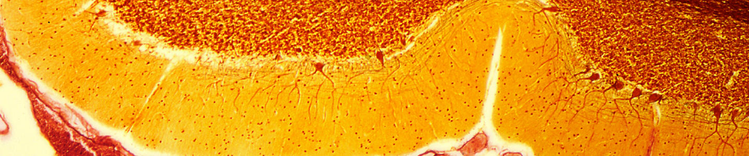

PURKINJEZELLEN IM KLEINHIRN

Veränderungen im alternden Gehirn

Zu den physischen Veränderungen des Gehirns, die mit dem Altern einhergehen, gehören:

- Atrophie (Schrumpfung) des Gewebes in einigen Regionen

- erhöhtes Ventrikelvolumen

- Verlust von Neuronen und Synapsen und verminderte Bildung neuer Neuronen

- Anhäufung von abnormen Proteinen